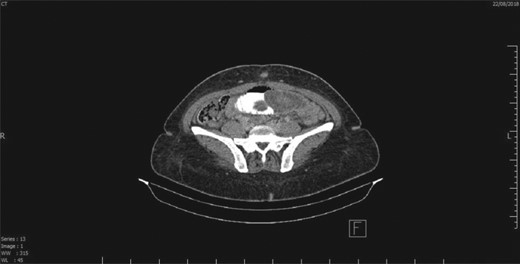

Intussusception of small intestine toward jejuno-jejunal anastomosis.

This is a case of a 46-year-old female, 3 years post REYGB. She presented to the emergency department with sudden abdominal pain as well as nausea and vomiting, which started the day before presentation (30 minutes post prandial). Moreover, on physical examination, the abdomen was soft with pain out of proportion (severe pain with minimal tenderness) and no other signs of peritoneal irritation. Furthermore, laboratory data were unremarkable. Abdominal computed tomography (CT) revealed a long segment of obstructed retrograde small bowel obstruction adjacent to the jejuno-jejunal anastomosis associated with a complete proximal small bowel obstruction (Fig. 1). Therefore, the patient was immediately taken to the operating room, and laparoscopic exploration of the abdomen was performed. A segment of retrograde jejuno-jejunal intussusception was encountered with dilated small bowel proximal to the intussusception and a collapsed part distal to it. Decision was made to convert the procedure to an open surgery through a small midline laparotomy (Fig. 2), and a trial was performed to undo the intussusception. There was a gangrenous segment of about 23 cm, necessitating resection and anastomosis (Fig. 3). The anastomosis was performed using a gastrointestinal anastomosis stapler device. Consequently, the patient tolerated the procedure well, and she was sent for recovery in a good condition. Pathology confirmed a gangrenous jejunal segment with features consistent with external venous compression (intussusception related) with viable surgical resection margins. Afterwards, the patient was discharged on postoperative day 3 in a good condition, and she remained asymptomatic during the follow-up period of 1 year.